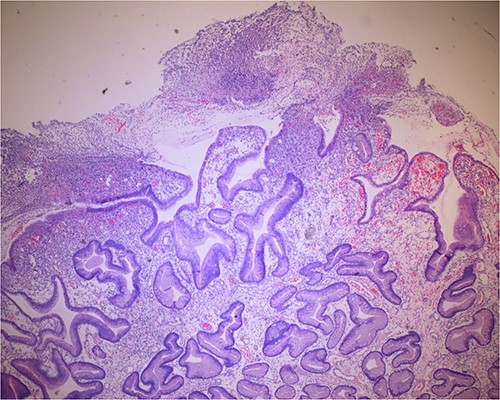

Histologic sections of the polyps demonstrated benign gastric hyperplastic polyps with acute and chronic gastritis (Fig. 2). Portions of the gastric polyps and adjacent mucosa were covered by inflammatory cell exudate (Fig. 3). Higher magnification revealed conspicuous volcanic-like eruption of the exudate, reminiscent of pseudomembranous gastritis (Fig. 4). Alcian yellow and GMS stains were negative for Helicobacter pylori and fungal organisms, respectively.

Biopsy of the polyp, covered in part by pseudomembranous inflammatory exudate.

Volcanic-like eruption of inflammatory exudate, reminiscent of pseudomembranous gastritis.